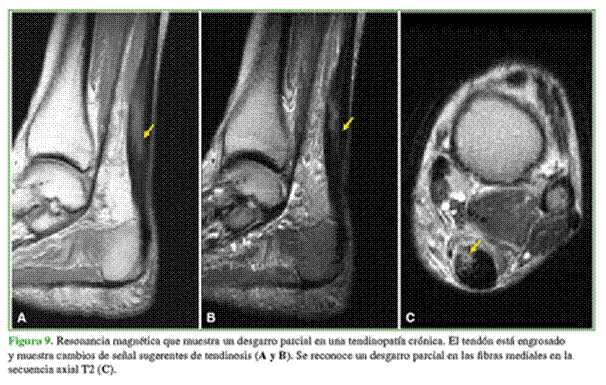

En la tendinopatía crónica, está alterado el grosor del tendón, la estructura es anormal, la ecografía muestra un patrón irregular con áreas de baja ecogenicidad y la RM, una señal modificada (Figuras 9 y 10).